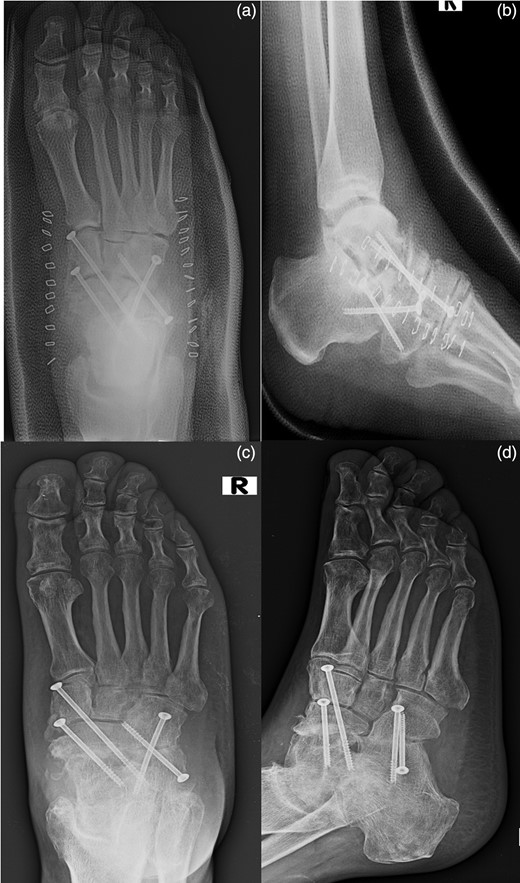

In August 2012, a 49-year-old-man presented to our hospital with a traumatic forefoot subamputation after a work accident. The trauma caused a lacerated wound in correspondence of the dorsal surface of the right foot. Radiographs and computed tomography (CT) examination confirmed the diagnosis of the loss of talus head during the trauma (Fig. 1).

AP (a) and lateral (b) radiographs and CT images (c, d) confirm the diagnosis of the loss of talus head during the trauma.